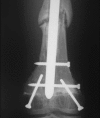

Although functionally appealing in preserving the native knee, the condyle-sparing intercalary allograft of the distal femur may be associated with a higher risk of tumor recurrence and endoprosthetic replacement for malignant distal femoral bone tumors. We therefore compared the risk of local tumor recurrence between patients in these two types of reconstruction groups. We retrospectively reviewed 85 patients (mean age, 22 years; range, 4-82 years), 38 (45%) of whom had a condyle-sparing allograft and 47 (55%) of whom had endoprostheses. The minimum followup for both groups was 2 years (mean, 7 years; range, 2-19 years). Local recurrences occurred in 11% (five of 47) of the patients having implants versus 18% (seven of 38) of the patients having allografts. Using time to local recurrence as an end point, the Kaplan-Meier survivorship of the implant group was similar to that of the condyle-sparing allograft group at 2, 5, and 10 years (93% versus 87% at 2 years, 87% versus 81% at 5 years, and 87% versus 81% at 10 years, respectively). The condyle-sparing allograft procedure offers the potential advantage of retaining the native knee in a young patient population while incurring no greater risk of local recurrence as those offered the endoprosthetic procedure.